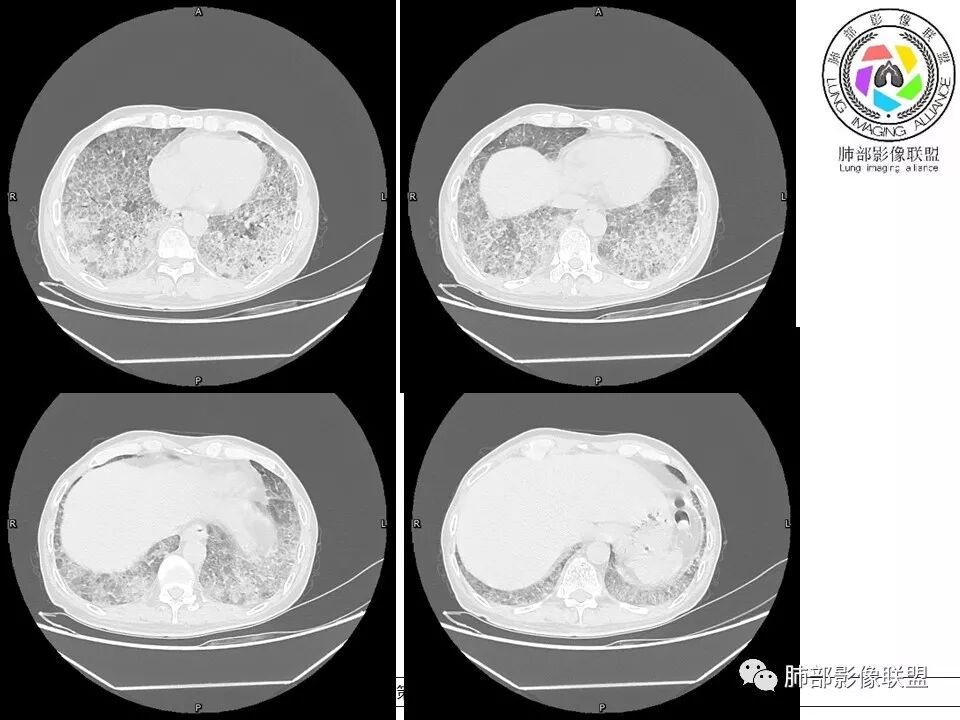

上肺为主小叶中心型肺气肿——吸烟

碎石路征,下肺为主

肺血坠积

5、病灶较多时部分可见重力趋势

1.由于脂蛋白的沉积和占据,肺泡腔含气量减少,这是影像上较大范围“磨玻璃影”的基础。

2.由液体、细胞浸润和纤维组织造成的小叶间隔增厚是影像上多边形“铺路石征”的基础。

4.病灶常多发,但心尖区及膈角区相对轻微。

5.部分病例显示有局部实变影